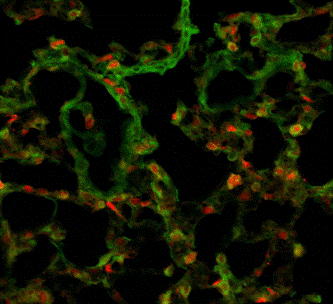

1) Depilation, wrinkled skin, hunchback and sharp decline of weight were observed in 8/13 mice. Routine blood test implicated hematopoietic reconstitution. FACS showed 86.1%±7.8% mRFP+ cells in peripheral blood of recipients. 2) mRFP+ cells were found distributing throughout the body's organs. mRFP+ Lymphocyte infiltration and inflammatory exudate were seen especially in the small intestine, lung, liver and skin (Fig.1). GFP+ cells were found surrounding mRFP+ cells in the bone marrow of the femora decalcified with semi-solid decalcification. Their interactions can be further observed clearly in bone marrow microenvironment in three-dimensional reconstruction by confocal microscope (Fig.2).

The donor and recipient cells' morphous, location, ratio and cellular interaction can be visually observed in recipient mice's lung under confocal microscope (250x).

The donor and recipient cells' morphous, location, ratio and cellular interaction can be visually observed in recipient mice's lung under confocal microscope (250x).